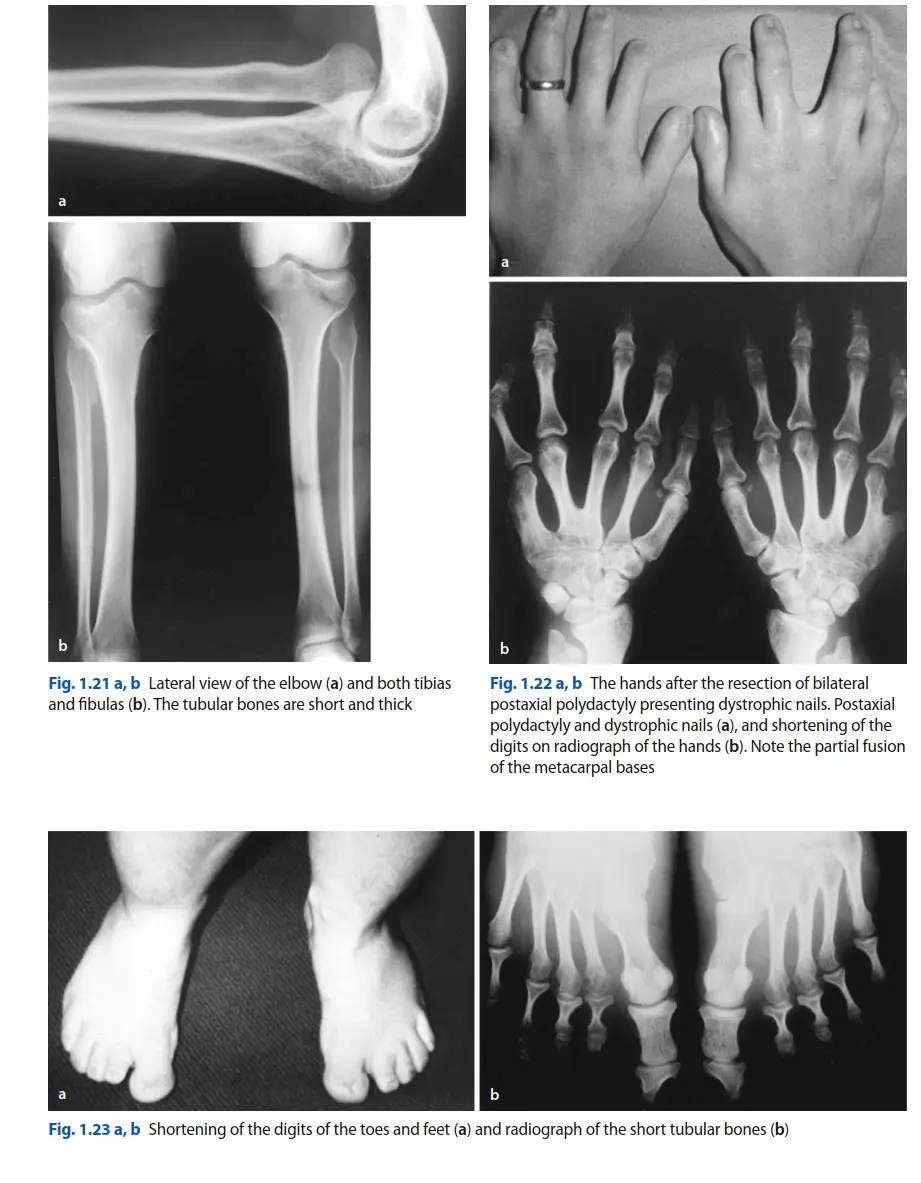

- خلع رأس الكعبرة (Radial Head Dislocation): يُعد خلع رأس عظم الكعبرة (أحد عظمي الساعد) بشكل أمامي أو خلفي سمة معروفة، مما يؤثر على نطاق حركة الكوع وقد يؤدي إلى تشوه مميز في المرفق. قد يكون غير مؤلم في البداية ولكنه قد يصبح مؤلمًا أو يحد من الوظيفة مع التقدم في العمر.

- الأشعة السينية (X-rays): تُعد الأشعة السينية للعظام الطويلة واليدين والقدمين والحوض والعمود الفقري ضرورية لتحديد مدى التشوهات الهيكلية. تُظهر الأشعة السينية قصر العظام، وشكل الصفائح النموية، ووجود الأصابع الزائدة، وتشوهات المفاصل مثل خلع الورك أو الركبة الروحاء.